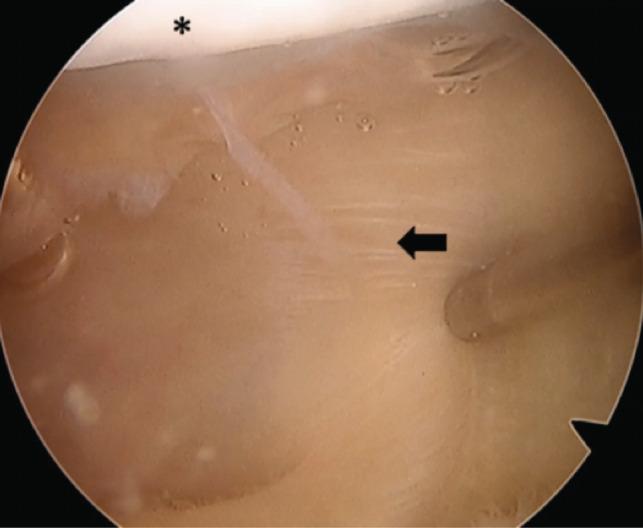

We report on a 19-year-old female patient who was diagnosed with a complete suprapatellar plica syndrome. She underwent arthroscopic excision of the plica. Post-operatively, there was complete resolution of the symptoms, with return to sports activity. A complete suprapatellar plica is a rare condition that separates the suprapatellar pouch from the rest of the knee. Cases of symptomatic complete suprapatellar plica should be managed with conservative measures initially. If conservative therapy fails, surgical arthroscopic excision is required.

我们报告了一名19岁女性患者,她被诊断为完全性髌上滑膜皱襞综合征。她接受了关节镜下滑膜皱襞切除术。术后症状完全缓解,恢复了体育活动。完全性髌上滑膜皱襞是一种罕见的疾病,它将髌上囊与膝关节的其余部分分隔开。有症状的完全性髌上滑膜皱襞病例最初应采用保守措施治疗。如果保守治疗失败,则需要进行手术关节镜切除。